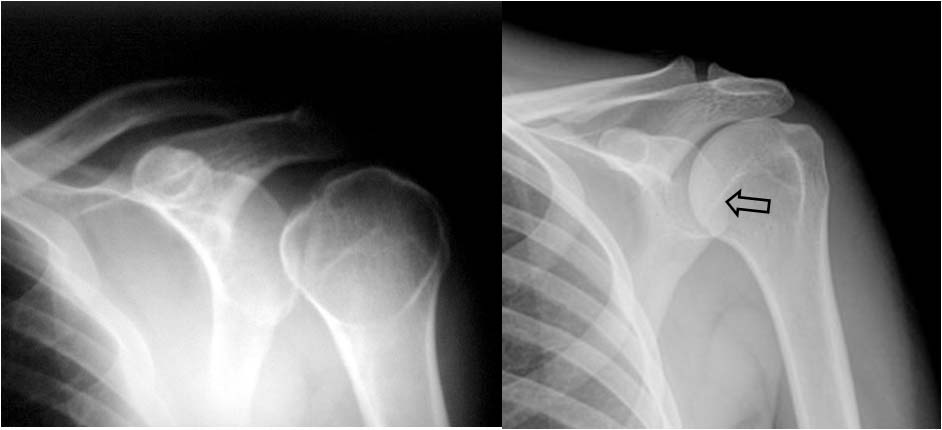

Signo de subluxación inferior de la cabeza humeral, asociada a menudo a fractura, visible en la radiografía anteroposterior del hombro. La cabeza humeral está descendida, pero no existe luxación anterior o posterior del hombro. Suele asociarse a fractura del cuello humeral y es debida a hemartros o lesión músculo-ligamentosa asociada. También existen causas no traumáticas de hombro caído, como la hemiplejia o el compromiso del plexo braquial por un tumor.

La imagen muestra el signo en una luxación humeral (a la izquierda -flecha-) y una radiografía normal del hombro en la que se ve la posición de la cabeza humeral y su relación con la superficie articular eacapular y con la clavícula (a la derecha).

En la radiografía anteroposterior de hombro normal, la cabeza humeral se solapa a la cavidad glenoidea, creando una imagen de semiluna. A la derecha podemos ver este hallazgo, marcado con la flecha negra.

En cambio, esta semiluna está ausente en la luxación posterior del húmero, tal como vemos en la fotografía de la izquierda.